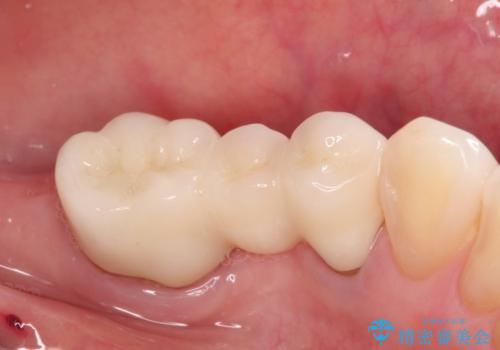

金属のかぶせ物をセラミックへ 根管治療からの再治療

左側の上下の奥歯に適合が悪く、レントゲン上でも根の治療が必要なところがありました。

根管治療からの再治療を行ったことにより、治療期間が多少長くなりましたが、今後再治療の必要性があまりないような、精度の高い治療ができました。